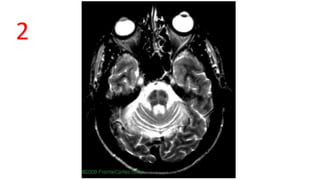

HOT-CROSS-BUN SIGN

Axial T2, Crucifrom hyperintensities in Pons

Due to selective loss of myelinated transverse

pontocerebellar fibers with preservation of the pontine

tegmentum and corticospinal tracts.

Seen in MSC-C, SCA 2,3, vCJD, PML, 2° Parkinsonism